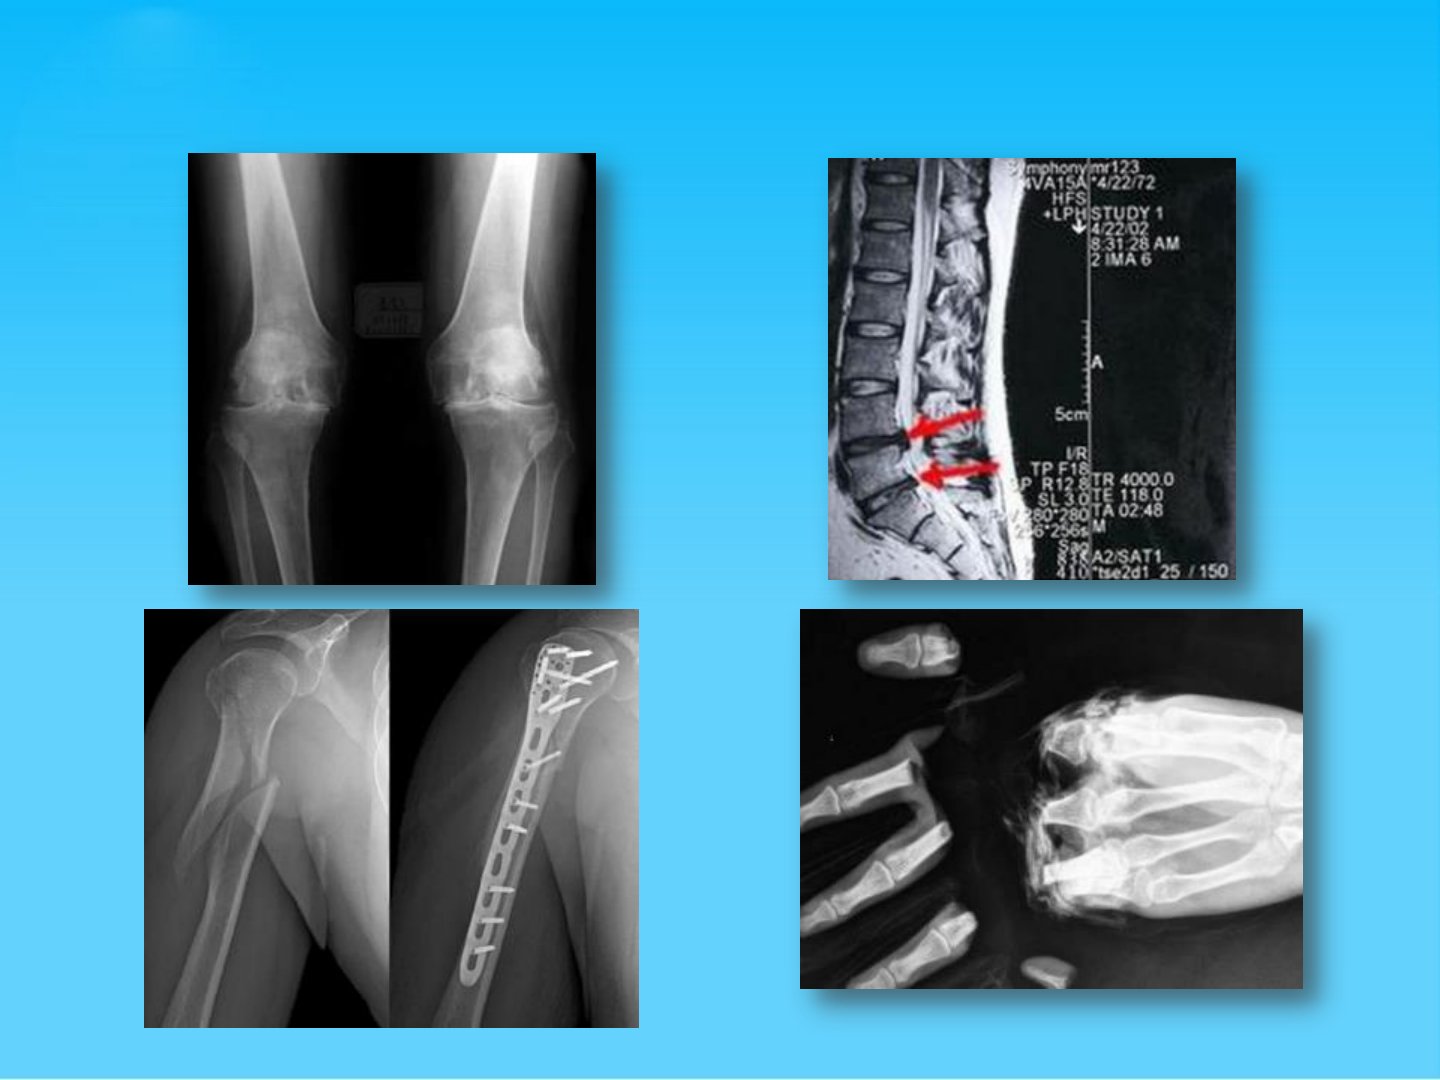

骨科常见疾病概述关节外科常见疾病概述关节外科常见疾病膝关节骨性关节炎股骨头坏死冻结肩(肩周炎)肱骨外上髁炎(网球肘)类风湿性关节炎一、膝关节骨性关节炎(OA)定义:各种机械性及生物性因素作用,造成膝关节软骨细胞、细胞外基质和软骨下骨合成与降解失衡,从而导致关节软骨软化、减少,软骨下骨硬化,骨赘形成和软骨下骨囊肿流行病学病因与发病机制老龄化:年龄增大增加了OA的危险性,但OA并非衰老的必然结果软骨细胞与基质合成代谢平衡被破坏:软骨组织包围在蛋白多糖的基质中,代谢平衡受生长因子及酶的调节,任何介质的改变均可引起OA免疫反应:当软骨微屑掉入滑膜后,局部淋巴细胞将其识别为抗原而发生自身免疫滑膜炎,这个...